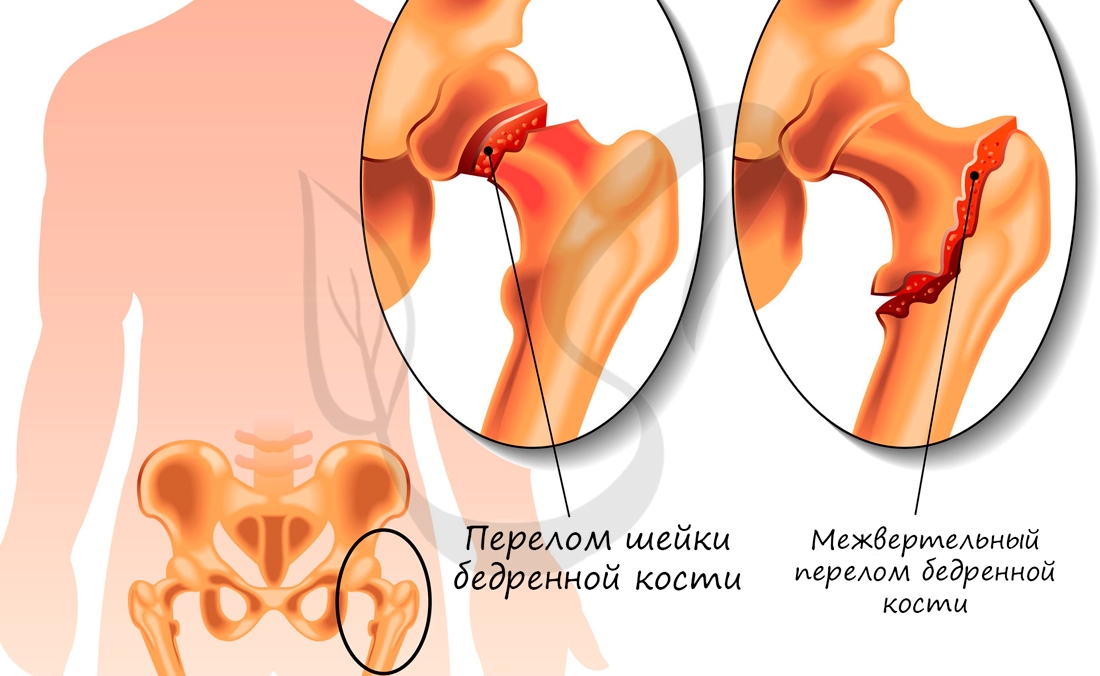

В норме кости могут смещаться относительно друг друга в суставе, однако при травме, слишком резком и сильном движении это смещение может быть слишком сильным: в результате нарушается соприкосновение суставных поверхностей. В таком случае говорят о возникновении вывиха.

Перед вправлением вывиха следует делать рентгенологическое исследование, чтобы убедиться в отсутствии переломов костей, которые иногда сопутствуют вывиху.

Переломы костей

Бедренная кость — самая крупная трубчатая кость в теле. Головка бедренной кости присоединяется к телу кости посредством шейки, которая расположена под различным углом у мужчин (130°) и у женщин (100°). Женская походка с раскачиванием бёдер связана как раз с этим отличием.